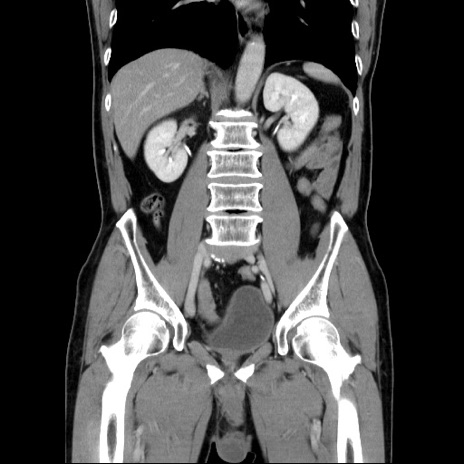

症例34(冠状断像)

【症例】60歳代 男性

【主訴】右鼠径部膨隆

【現病歴】1年程前より右鼠径部膨隆あり。自己にて還納可能だったため放置していた。3時間前より右鼠径部の脱出を認め、還納困難となり受診。

【既往歴】高血圧

【身体所見】右鼠径部に小児頭大の膨隆あり。弾性硬であり、用手還納は困難。左鼠径部にも膨隆を認める。脱出はなし。